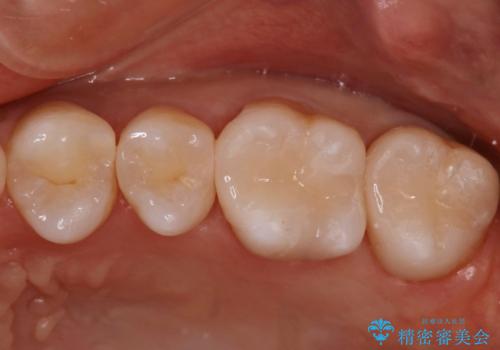

- 銀歯が気になるということで来院された患者様です。

セラミックでの治療を希望されたので治療をいたしました。

銀歯は長い間使用していると隙間ができて、虫歯の原因になります。

そのため適合の良いセラミックをお勧めいたします。